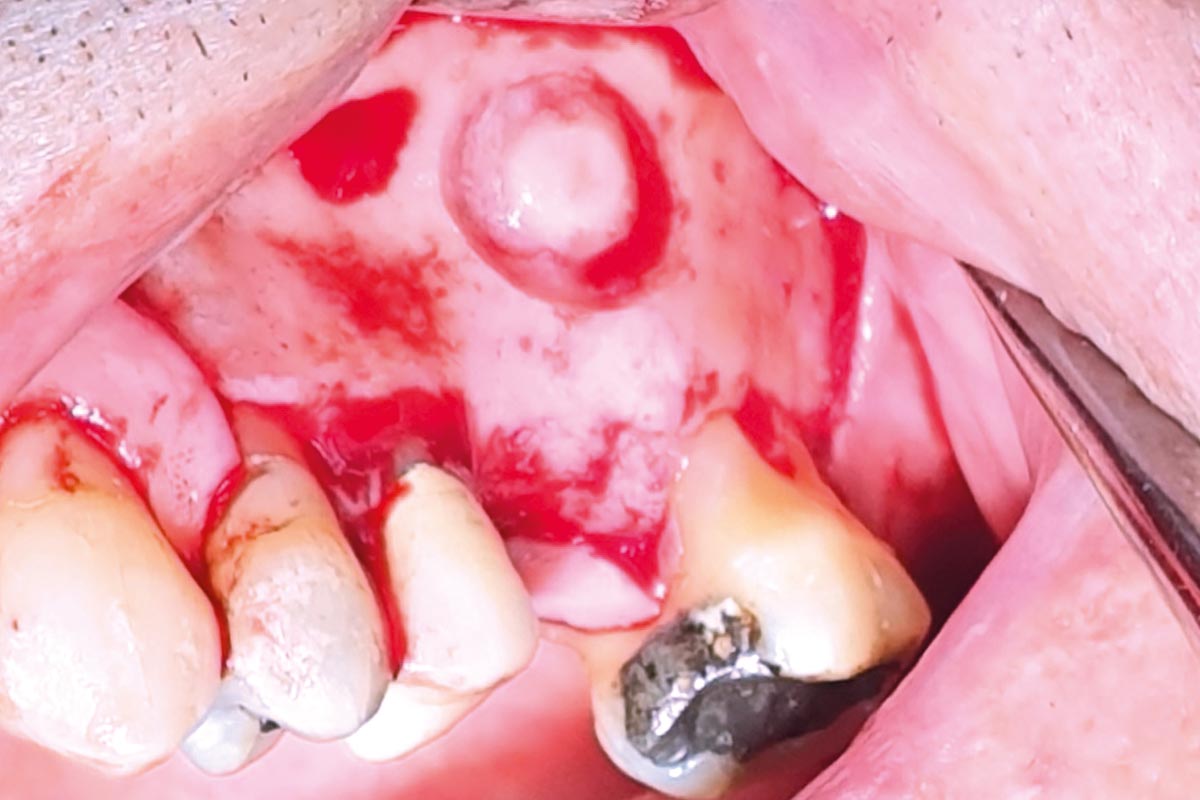

18/35 - Re-opening of the flap for lateral sinus lift and implant positioningMaxillary sinus cyst removal using the Crocodile Technique and subsequent lateral sinus lift - Dres. C. Scognamiglio and A. Perucchi